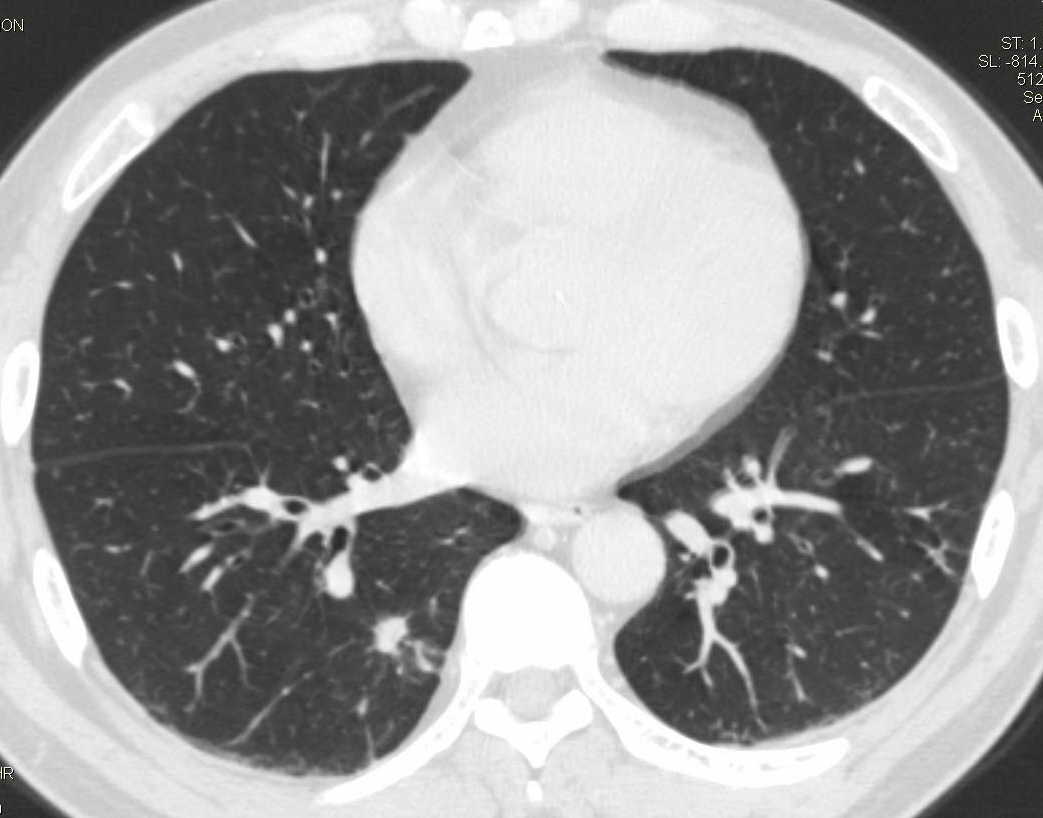

标题: CT15857:男性 58岁 咳痰带血 无发热 请各位大侠发表一下意见 [打印本页]

标题: CT15857:男性 58岁 咳痰带血 无发热 请各位大侠发表一下意见

两肺下叶肺纹理增多、增粗并呈“树芽状”改变。支气管扩张呈囊状,部分呈柱状改变。其周围可见散在的斑片样及条索样密度增高影,右肺下叶近叶间胸膜可见一形态不规则的高密度结节影,并与胸膜粘连。

考虑:支扩并发感染。

双肺多发炎性病灶,结核可能性大,建议抗炎治疗复查.右肺下叶前基底段结节灶,高度警惕肺癌可能

双肺间质性改变(间质纤维化?)伴支扩。右肺下叶有毛刺的小结节,考虑周围型肺癌可能性。